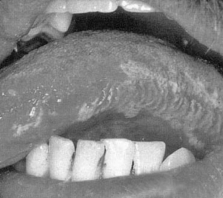

1.4.1.5.1一、症状及体征